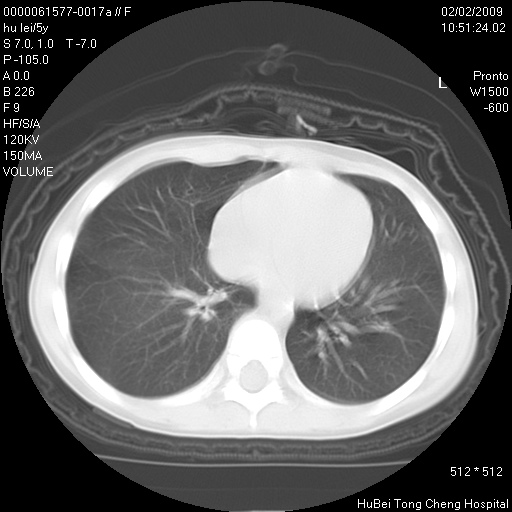

标题: PED1732:M5Y,右肺囊性占位!

患者:男,5。无明显不适,拍胸片考虑右肺囊肿。

行ct扫描,图象如下: